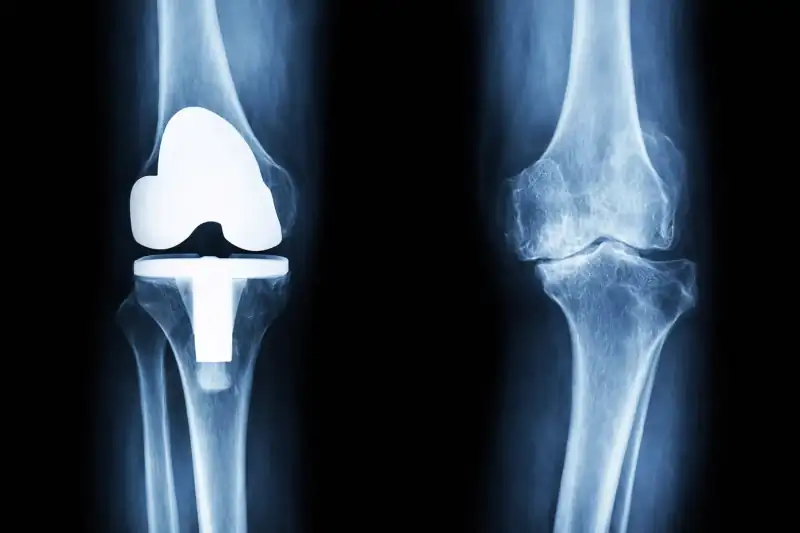

Chirurgia protesica del ginocchio test

Specialista in protesi di ginocchio con oltre 5000 interventi eseguiti

Chirurgia protesica di ginocchio ad alta personalizzazione

L'Unità Operativa di Ortopedia III di Villa Erbosa guidata la Professore Pipino Gennaro, si occupa di chirurgia protesica di ginocchio ad alta personalizzazione avvalendosi dell’utilizzo di mascherine su misura per le resezioni ossee.